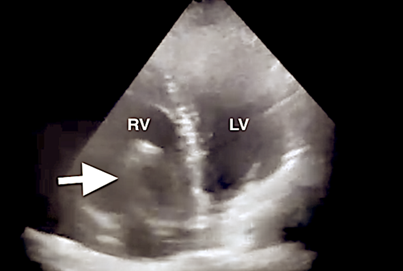

At the intensive care unit, patients were extubated approximately 8 hours after the operation with normal arterial blood gas tests and chest X-ray exams (figure 6 A, B). Catecholamine infusion was discontinued at the 36th hour, and patients were discharged on the 9th postoperative day.  Three years later, our patients are alive and in good condition, without embolism recurrence and with normal pulmonary artery pressure. Six months after operations, acenocoumarol was replaced with NOAC.

Figure 6 Postoperative chest X-ray after extubation showed normal findings. A. Case 1; B. Case 2.